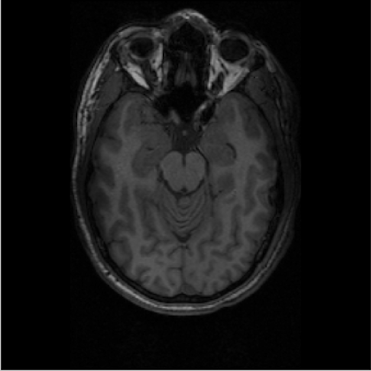

I used the Maker Hub 3D printers to print out a 1:1 scale model of my own brain after getting an MRI this past summer. Additionally, I printed the brains of about 26 participants in a neuroimaging study I was a research assistant for during Summer 2018. 3D printing helped facilitate my research by providing our 9-13 year old participants with scale models or their individual brains, both providing them with a physical reminder of the study and allowing them to feel involved.